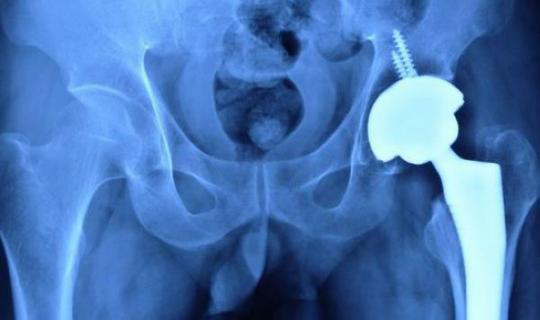

患者需提前1-2天入院,入院前空腹,術(shù)前采血,常規(guī)術(shù)前準(zhǔn)備,如無明顯手術(shù)禁忌癥,可給予手術(shù)治療,術(shù)后復(fù)查X線片。

術(shù)后復(fù)查X線片